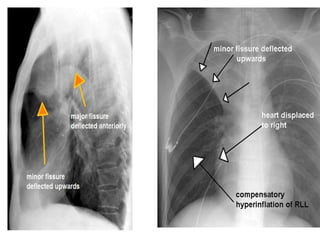

LOBAR ATELECTASIS

Radiologic signs of lobar atelectasis :- Direct

or Indirect .

Direct signs include increased opacification

of the airless lobe and displacement of

fissures.

Indirect signs include displacement of hilar and

cardiomediastinal structures toward the side of

collapse, narrowing of the ipsilateral intercostal

spaces, elevation of the ipsilateral

hemidiaphragm, compensatory hyperinflation

and hyperlucency of the remaining aerated

lung, and obscuration or desilhouetting of the

structures adjacent to the collapsed lung

(eg, diaphragm and heart borders). Additional

radiologic features vary according to the site of

atelectasis.